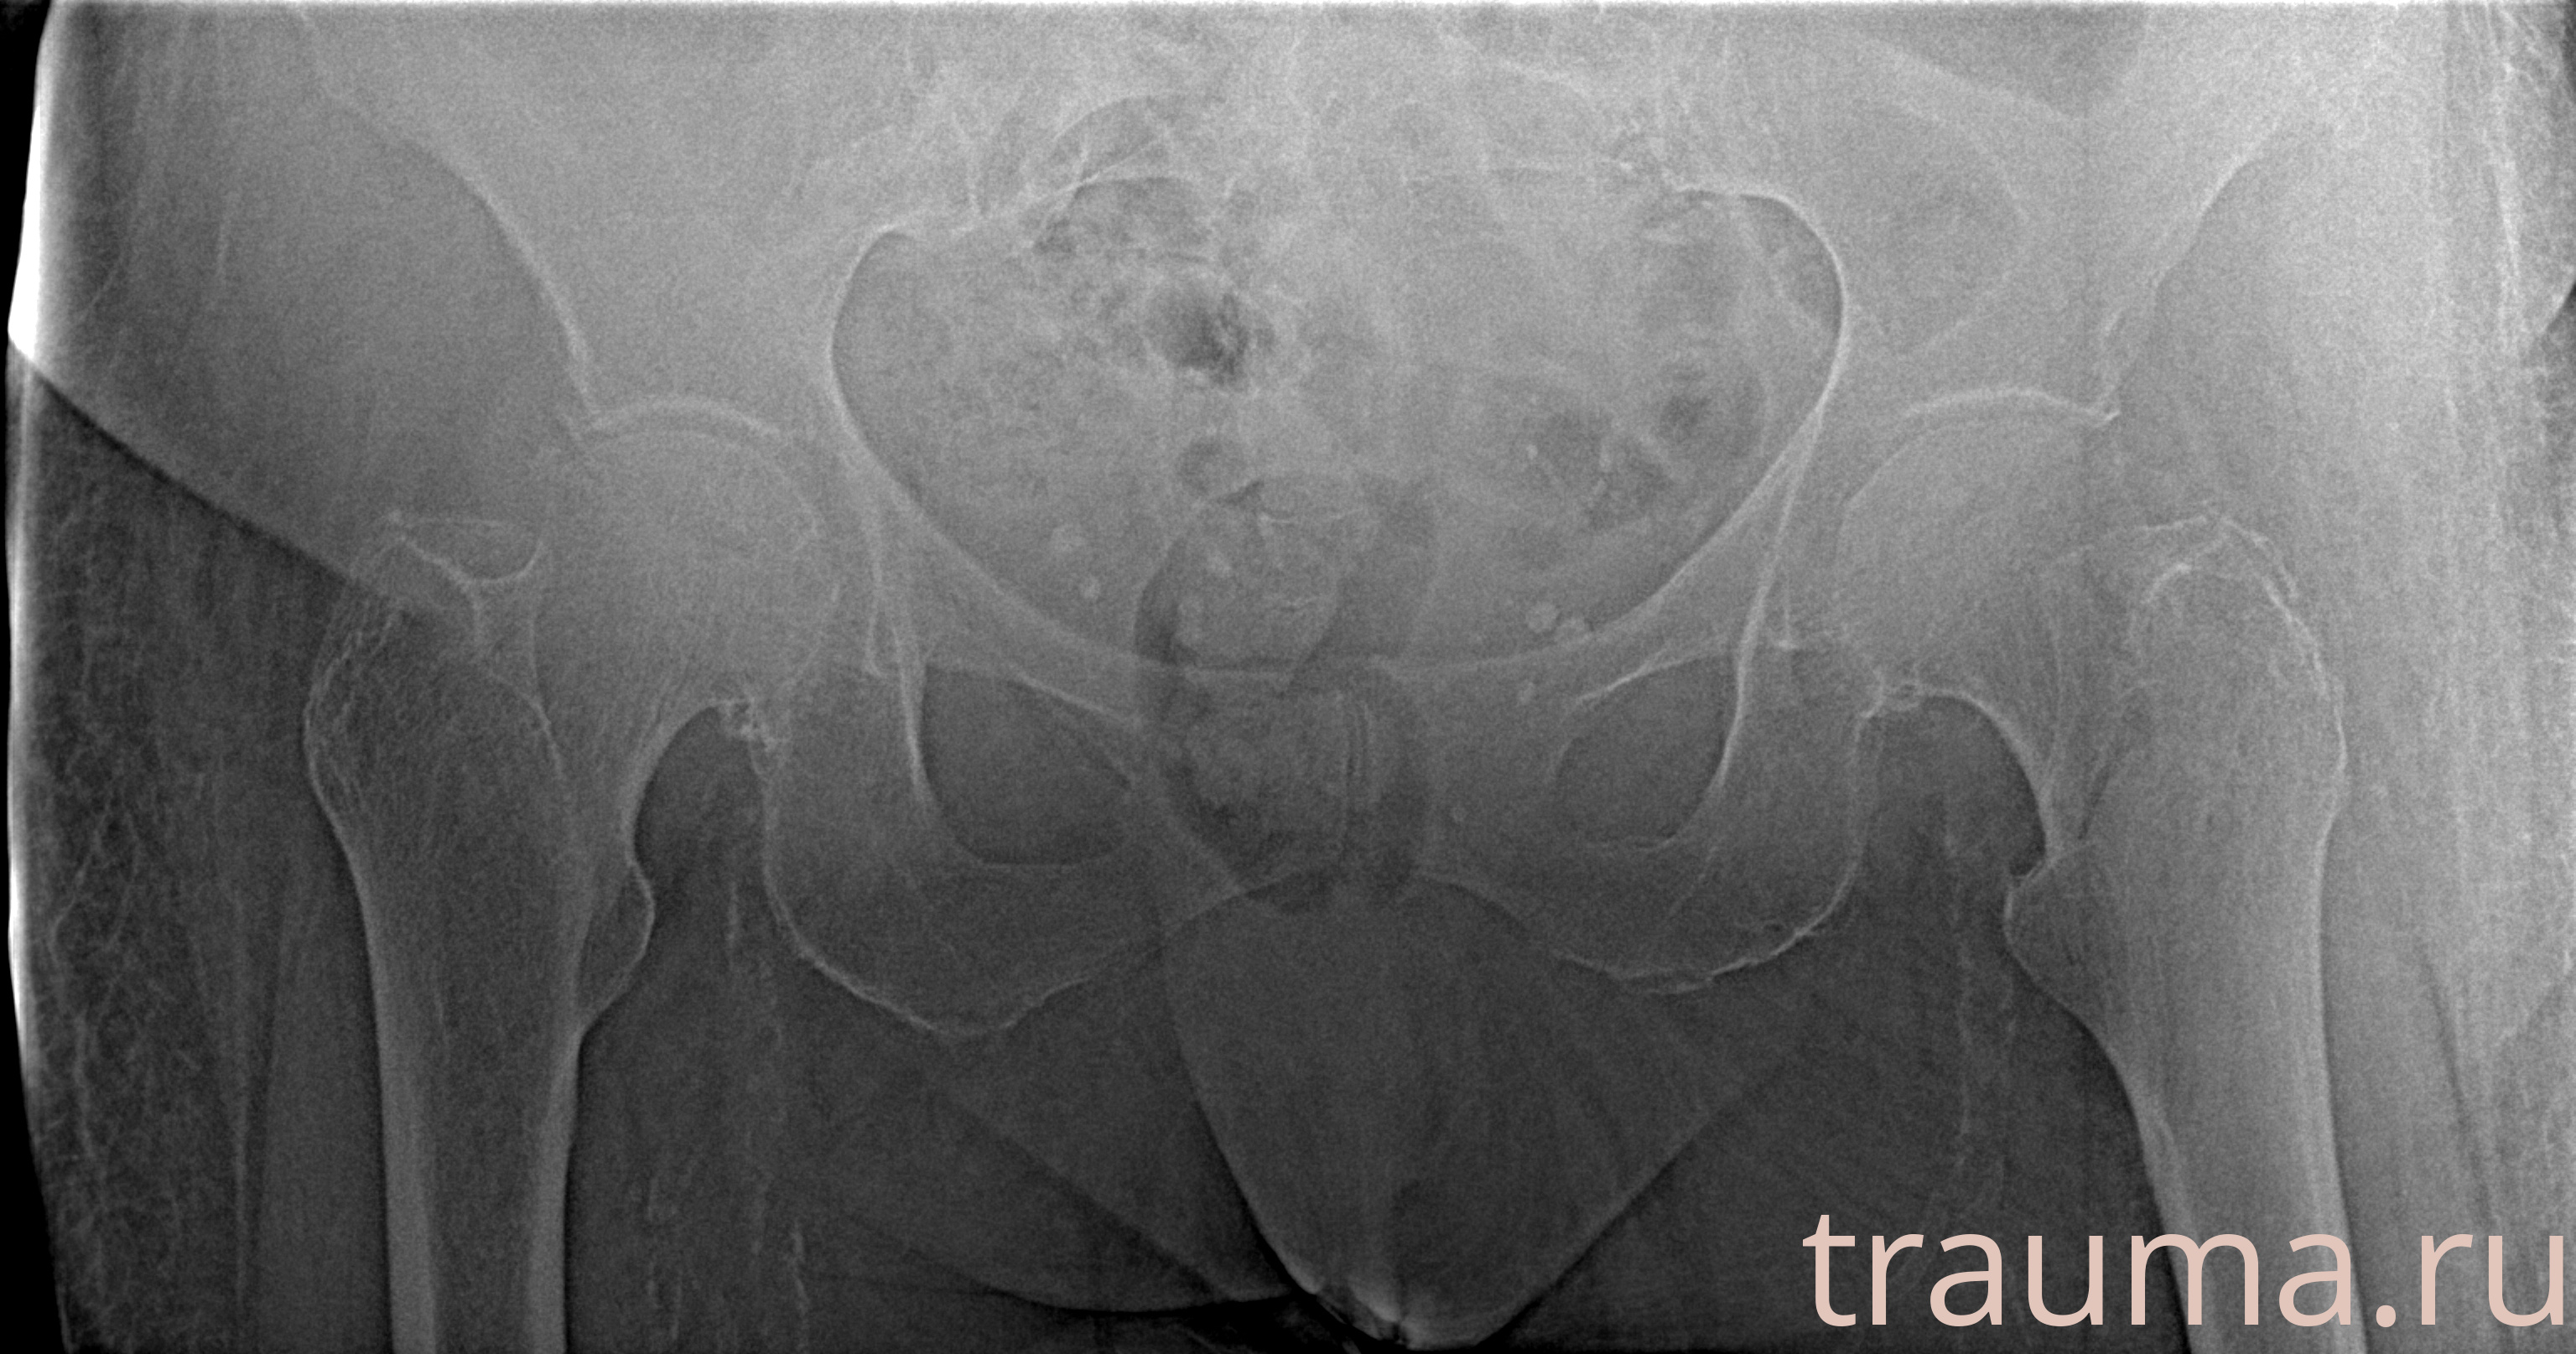

Рентген на дому: по вашему адресу приезжает врач-рентгенолог, травматолог-ортопед с мобильным рентгеновским аппаратом, проводит диагностику травмы или заболевания, делает необходимые рентгенограммы, дает рекомендации по дальнейшему лечению. Получить качественные снимки в домашних условиях возможно благодаря уникальной методике, разработанной МосРентген Центром для института  Склифосовского